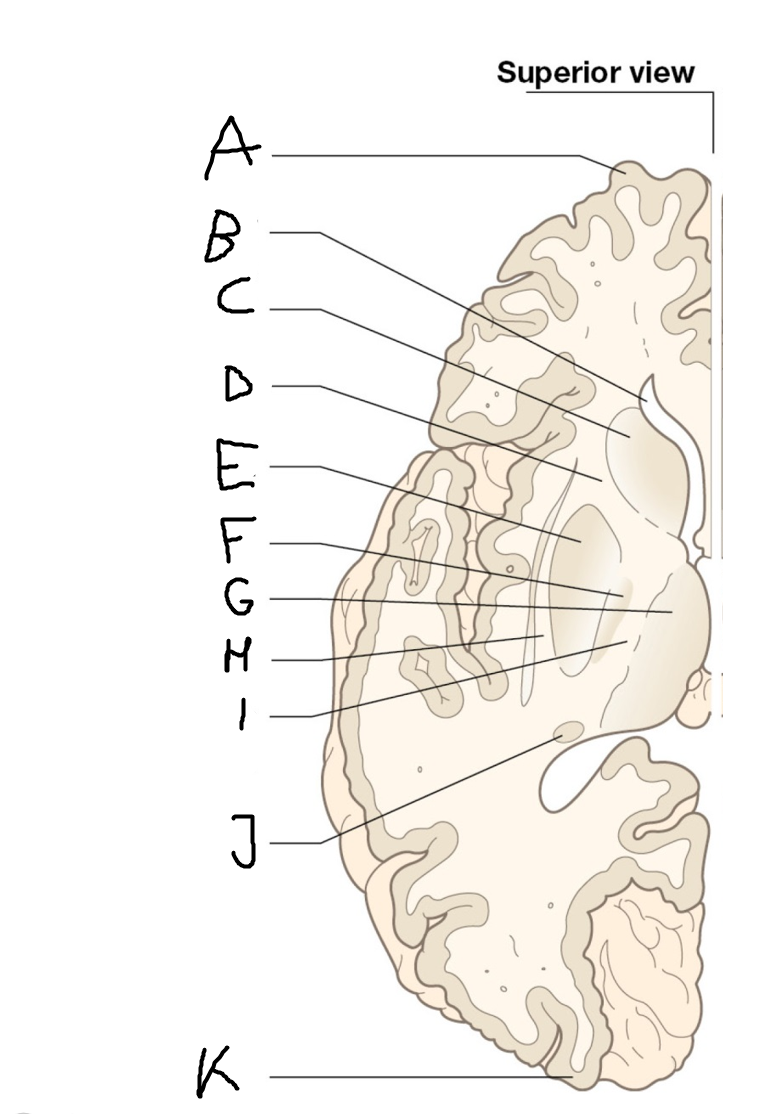

internal capsule (posterior limb)

B

anterior horn of lateral ventricle

C

head of caudate nucleus

D

internal capsule (anterior limb)

E

putamen

F

globus pallidus

G

Thalamus

H

External capsule

I

internal capsule (posterior limb)

J